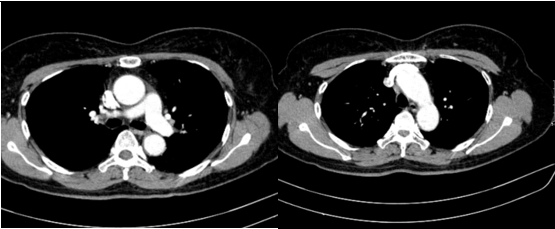

- Cắt lớp vi tính lồng ngực: đám xẹp đông đặc đỉnh phổi phải kích thước 11mm; nhu mô phổi rải rác nốt đặc 5-10mm. Trung thất cân đối có vài hạch 10mm

Hình 6: Hình ảnh cắt lớp vi tính ngực có tiêm: đám xẹp đông đặc đỉnh phổi phải kích thước 11mm (mũi tên xanh nước biển)

Hình 7: Hình ảnh cắt lớp vi tính ngực có tiêm: Trung thất cân đối có vài hạch 10mm (mũi tên vàng). Hạch trung thất giảm kích thước rất nhiều chỉ sau 03 chu kỳ.

- Cắt lớp vi tính lồng ngực: Đám xẹp vùng đỉnh phổi phải, nốt đặc nhỏ kích thước 2-3mm. Không thấy hạch to hay khối trong trung thất

Hình 10: Hình ảnh cắt lớp vi tính ngực có tiêm: Đám xẹp vùng đỉnh phổi phải, nốt đặc nhỏ kích thước 2-3mm

Hình 11: Hình ảnh cắt lớp vi tính ngực có tiêm: Không thấy hạch to hay khối trong trung thất

Nhận xét: Chỉ sau 03 chu kỳ Pemetrexed – Carboplatin – Pembrolizumab, hình ảnh chụp cắt lớp vi tính cho thấy tổn thương phổi nguyên phát và các hạch giảm kích thước đáng kể. Đáp ứng điều trị được đánh giá là đáp ứng một phần theo tiêu chuẩn RECIST 1.1. Sau 9 chu Pemetrexed – Pembrolizumab, bệnh nhân tiếp tục ghi nhận cải thiện rõ rệt các triệu chứng lâm sàng, thể trạng ổn định, không xuất hiện tác dụng không mong muốn nghiêm trọng.Đánh giá trên hình ảnh chụp cắt lớp vi tính cho thấy tổn thương phổi nguyên phát tiếp tục giảm kích thước không ngấm thuốc chỉ còn là đám xơ xẹp vùng đỉnh phổi phải, các hạch trung thất và ngoại vi thu nhỏ rõ rệt, không phát hiện được trên phim chụp và không ghi nhận tổn thương di căn mới.